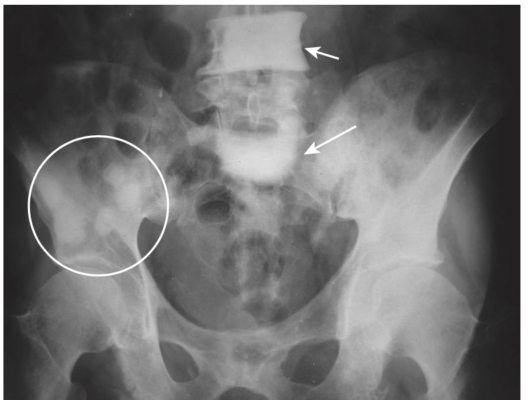

- Bệnh di căn tạo xương, giống như từ tuyến tiền liệt, có thể làm tăng khu trú về mật độ xương, cũng như tăng toàn thể.

- Một chất được tiết từ các tế bào u của ung thư biểu mô tuyến tiền liệt có thể kích thích hoạt động của tạo cốt bào và tạo ra các vùng tăng đậm độ xương khu trú. Những tổn thương này thường thấy nhất ở đốt sống, xương sườn, xương chậu, xương đùi và xương đùi (Hình-5).